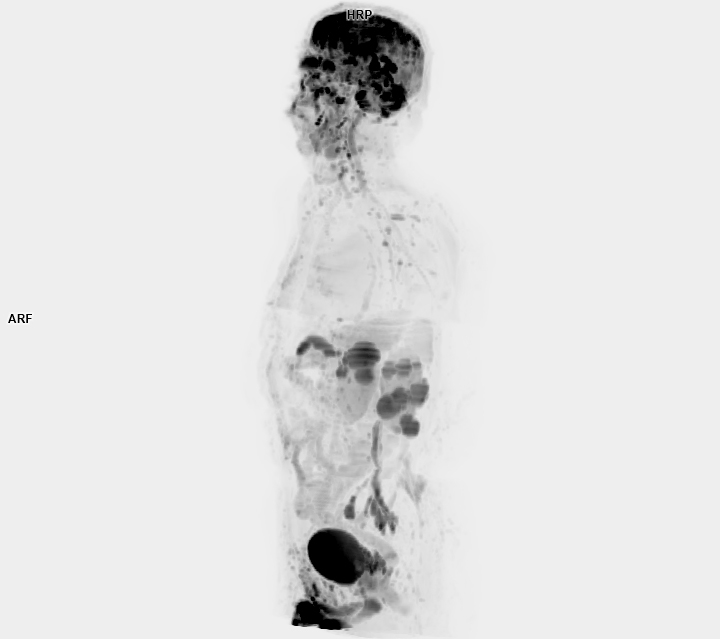

• 3 TESLA MR ÇEKİM GÖRÜNTÜLERİ

3 Tesla MR Çekim Görüntüleri

• 3 Tesla MR Çekim Görüntüleri